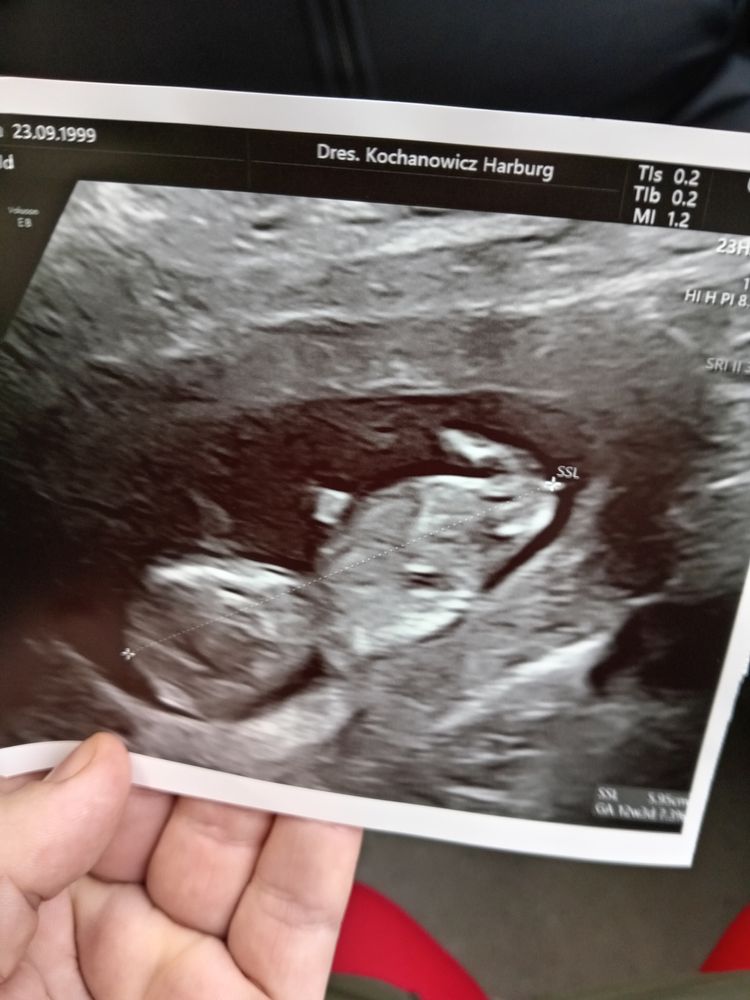

Вот у меня также было)) ну девочка же! Похоже)) Изображение

08.02.2024

Я за девочку! Не верные свои догадки сначала писала.. сравнила со своей фоткой в дневнике - пусть будет девочка!))) Изображение